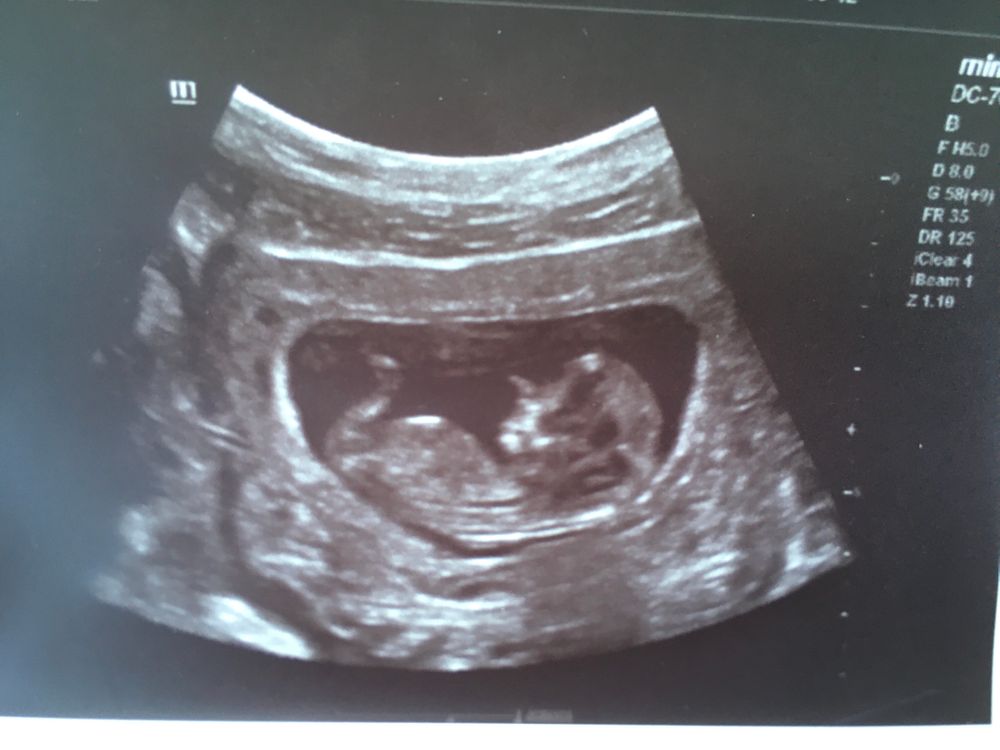

Бугорок не видно 🤷‍♀️ Изображение У нас чётко получилось на видео , сомнений не было

Девочка

Мальчик

Мальчик скорее всего, бугорок спрятан за ножкой